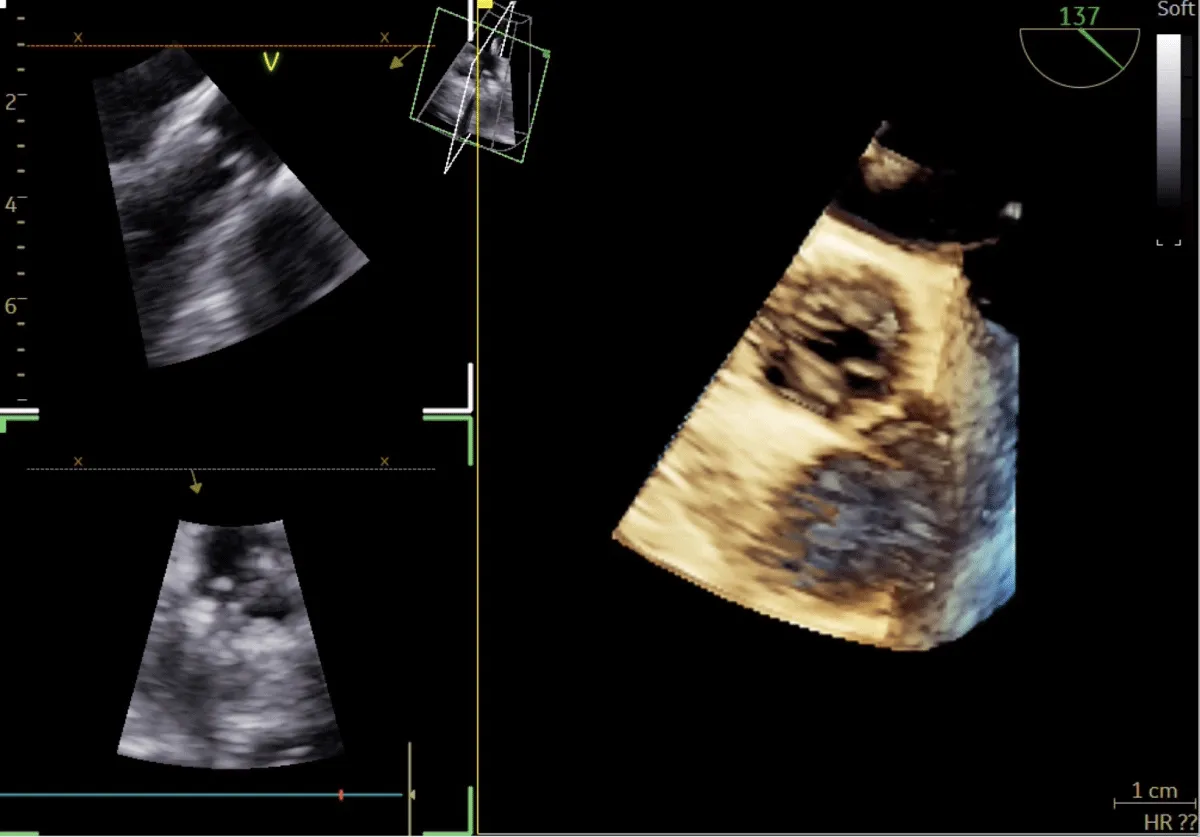

After obtaining consent, access was obtained through the right femoral vein and artery. Under 4D Transesophageal Echocardiography (4D TEE) guidance, the first transseptal puncture was performed with a broken Brough needle, and the LA wire was inserted through femoral venous access (Figure 1). Right femoral artery access was used for retrograde crossing of the aortic valve (AV) (Figure 2), and a Teflon wire was placed in the left ventricle. The aortic valve (AV) was dilated with a 14 mm ATLAS GOLD (BARD) balloon (Figure 3, Video 1).

Figure 1: A,B: 4Dimensional multiplanar transoesophageal echocardiography. A. 4D image with Left atrial wire, B. Severe mitral stenosis with mitral area of 0.5 cm2, 1C &1D. Showing multiplane of mitral valve.

Figure 2: 4Dimensional multiplanar transoesophageal echocardiography view of aortic valve.

Following a single dilatation, the AV gradient decreased from 82 mm Hg to 30 mm Hg without aortic regurgitation (AR). Subsequently, the mitral valve (MV) was dilated with a 26 mm Inoue balloon (Figures 4,5) (Video 2). After a single dilatation, the MV gradient was reduced from 35/21 mm Hg to 12/5 mm Hg, and the MV area increased from 0.5 cm2 to 1.6 cm2 (Figure 6)

Figure 5: 4Dimensional multiplanar transoesophageal echocardiography – Balloon dilatation of the mitral valve with Inoue balloon.

Figure 6: 4Dimensional multiplanar transoesophageal echocardiography – mitral valve after balloon dilatation.